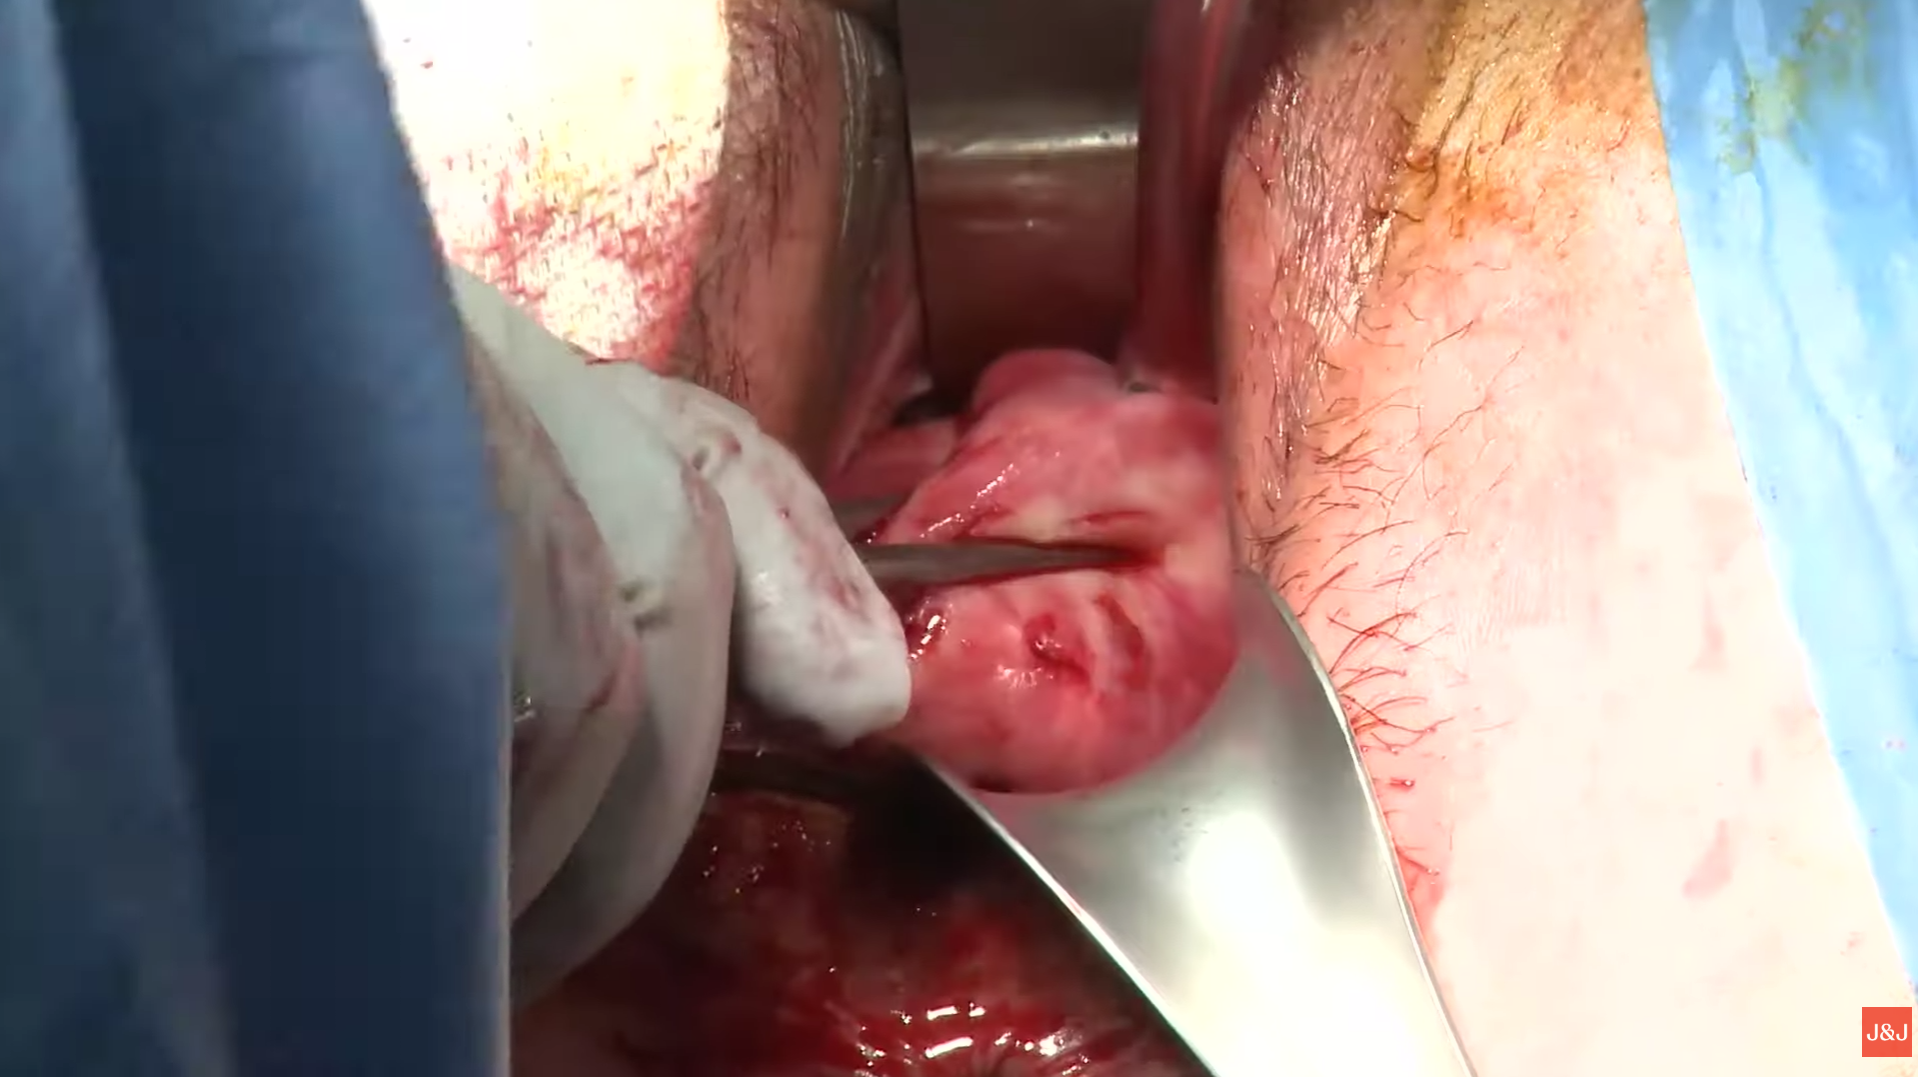

Cilt Grefti Uygulaması

Plastik Ve Rekonstrüktif Cerrahi

Ardian Kryeziu

Cilt Grefti Uygulaması

Plastik Ve Rekonstrüktif Cerrahi

Ardian Kryeziu

Cilt Grefti Uygulaması